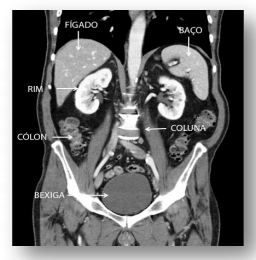

“Por seu papel contundente na detecção de diagnósticos clínicos, é necessário um profissional treinado para realizar a Tomografia Computadorizada, conhecimentos de Anatomia, Fisiologia, Radiologia, Física, entre outros, são cruciais para a formação do profissional e, posteriormente, para garantir uma imagem com qualidade para a abordagem clínica correta com o paciente” (MACIEL E JÚNIOR, 2015).

Observando a imagem acima e usando os conhecimentos sugeridos no trecho escrito escolha a opção que traz apenas as proposições verdadeiras.

I - A retirada do cólon, esplenectomia, pode ser importante em quadros complicados de digestão.

II - Ao contribuir diretamente com a hematose e enurese, o fígado executa outras inúmeras funções.

III - O rim promove o controle do equilíbrio hidroeletrolítico sendo a sede da filtração glomerular.

IV - O baço é o órgão que se lesiona com mais frequência no abdômen quando há pancadas violentas no lado esquerdo.